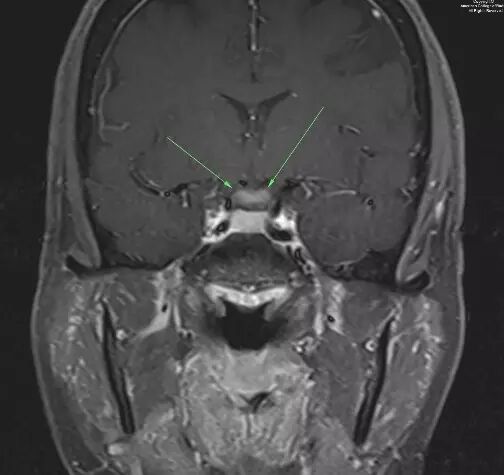

图 2. 增强T1示视交叉增粗并强化(箭头示)

图 3. 冠状增强T1视交叉增粗并强化(箭头示)